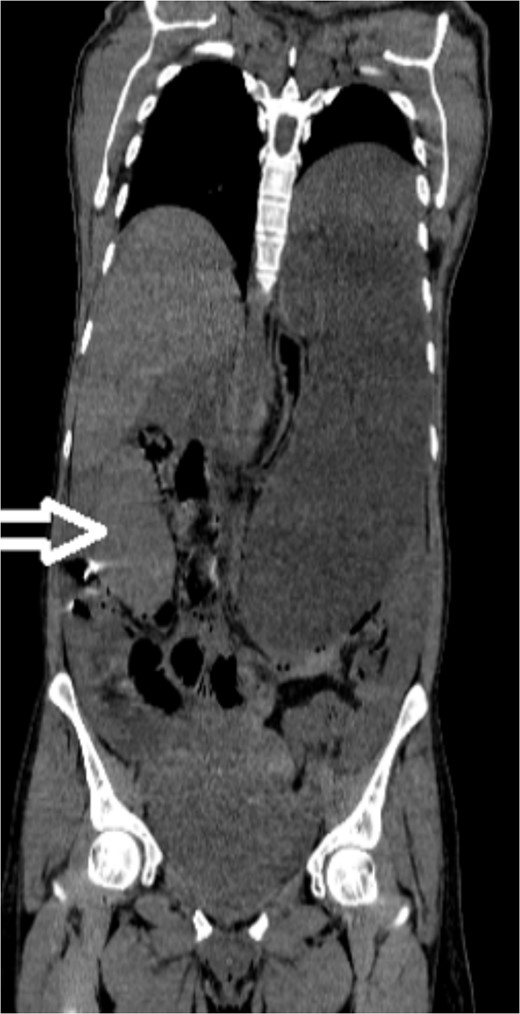

Upon admission to our hospital, the patient’s physical examination revealed hypotension (87/52 mmHg) and tachycardia (150 bpm), along with marked diffuse abdominal tenderness and guarding. Laboratory investigations indicated a hemoglobin level of 7.1 g/dl, a white blood cell count of 14.5 × 103 μl, and a platelet count of 202 × 103 μl. An abdominal CT scan without contrast showed an enlarged ectopic spleen measuring 18 cm in the right abdominal area, a distended stomach, a moderate volume of hemoperitoneum, and significant intra-abdominal fluid accumulation. CT findings are shown in Figs 1–3. Based on these findings, the patient was immediately transferred to the operating room.

Noncontrast coronal CT scan of the abdominopelvic area showing the spleen located in the right upper abdominal area.